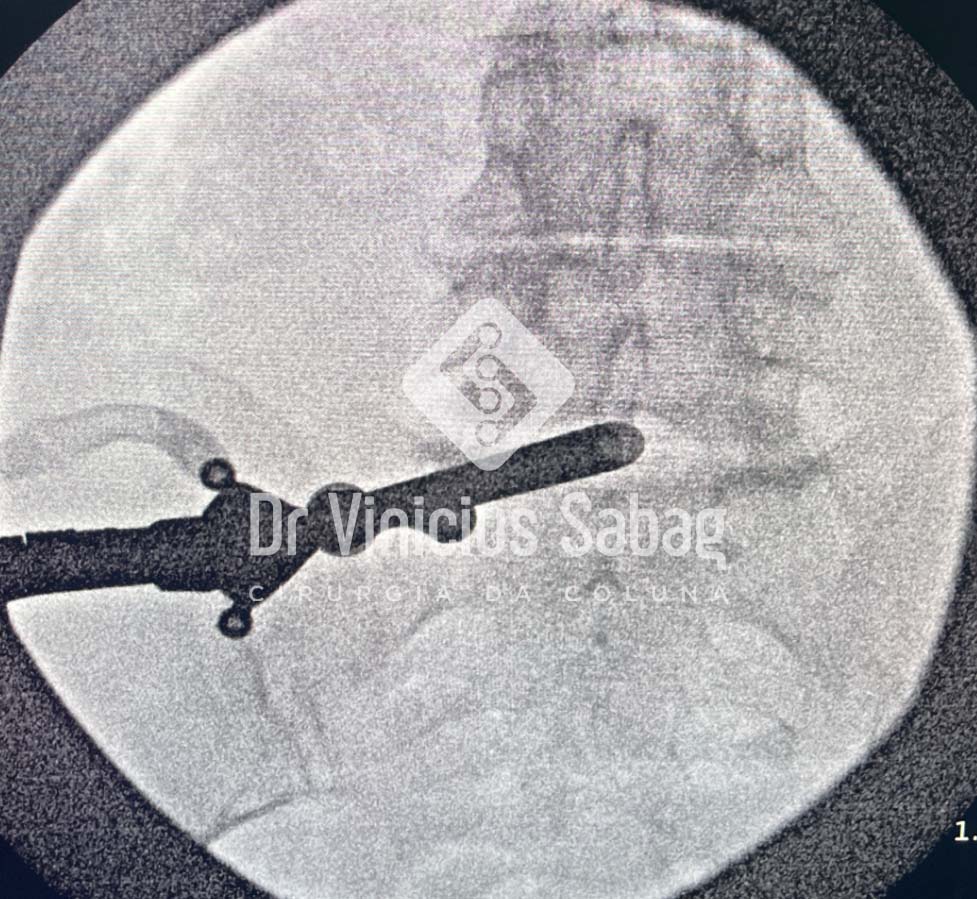

Imagem de raio-X intraoperatório utilizada para localização precisa do nível da hérnia discal durante a cirurgia minimamente invasiva.